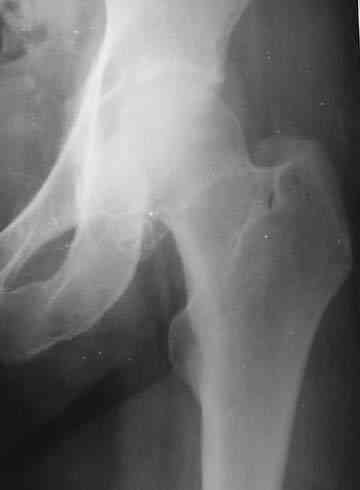

Боль постепенно усиливалась в течении последних 2 лет. Лечилась амбулаторно у невролога по месту жительства с диагнозом остеохондроз поясничного отдела позвоночника, корешковый синдром. В общих и биохимических анализах крови изменений не отмечалось, ревматоидный фактор (РФ), С-реактивный белок – в пределах нормы. Рентгенологическое исследование. В прямой и боковой проекции левого тазjбедренного сустава отмечается уплотнение крыши вертлужной впадины. В мягких тканях определяются округлой формы участки неравномерного обызвествления.Заключение. ДОА тазобедренного сустава. Хондроматоз слева в мягких тканях.Клиника. Видимых деформаций в области тазобедренного сустава нет. Ограничено отведение в левом тазобедренном суставе из-за болей до 20º. На основании клинических и лабораторных показателей был поставлен диагноз "Хондроматоз левого тазобедренного сустава". После стандартного предоперационного обследования выполнена диагностическая артроскопия тазобедренного сустава – обнаружены свободно лежащие внутрисуставные хондральные тела > 2 см в диаметре, хондромаляция хряща головки бедренной кости II степени. Выполнена боковая артротомия, внутрисуставные тела удалены, синовиальная оболочка частично резецирована. Послеоперационное течение – без осложнений. Швы сняты в срок, заживление первичным натяжением. Назначен курс лечебной физкультуры. Учитывая наличие рентгенологических признаков коксартроза, проведен курс внутрисуставной вискосуплиментарной терапии препаратами 1% гиалуроновой кислоты № 2.Осмотр через 1 месяц после оперативного лечения. Жалоб на боль при ходьбе нет, движения в полном объеме. Рекомендовано динамическое наблюдение раз в полгода и контрольная рентгенография через год